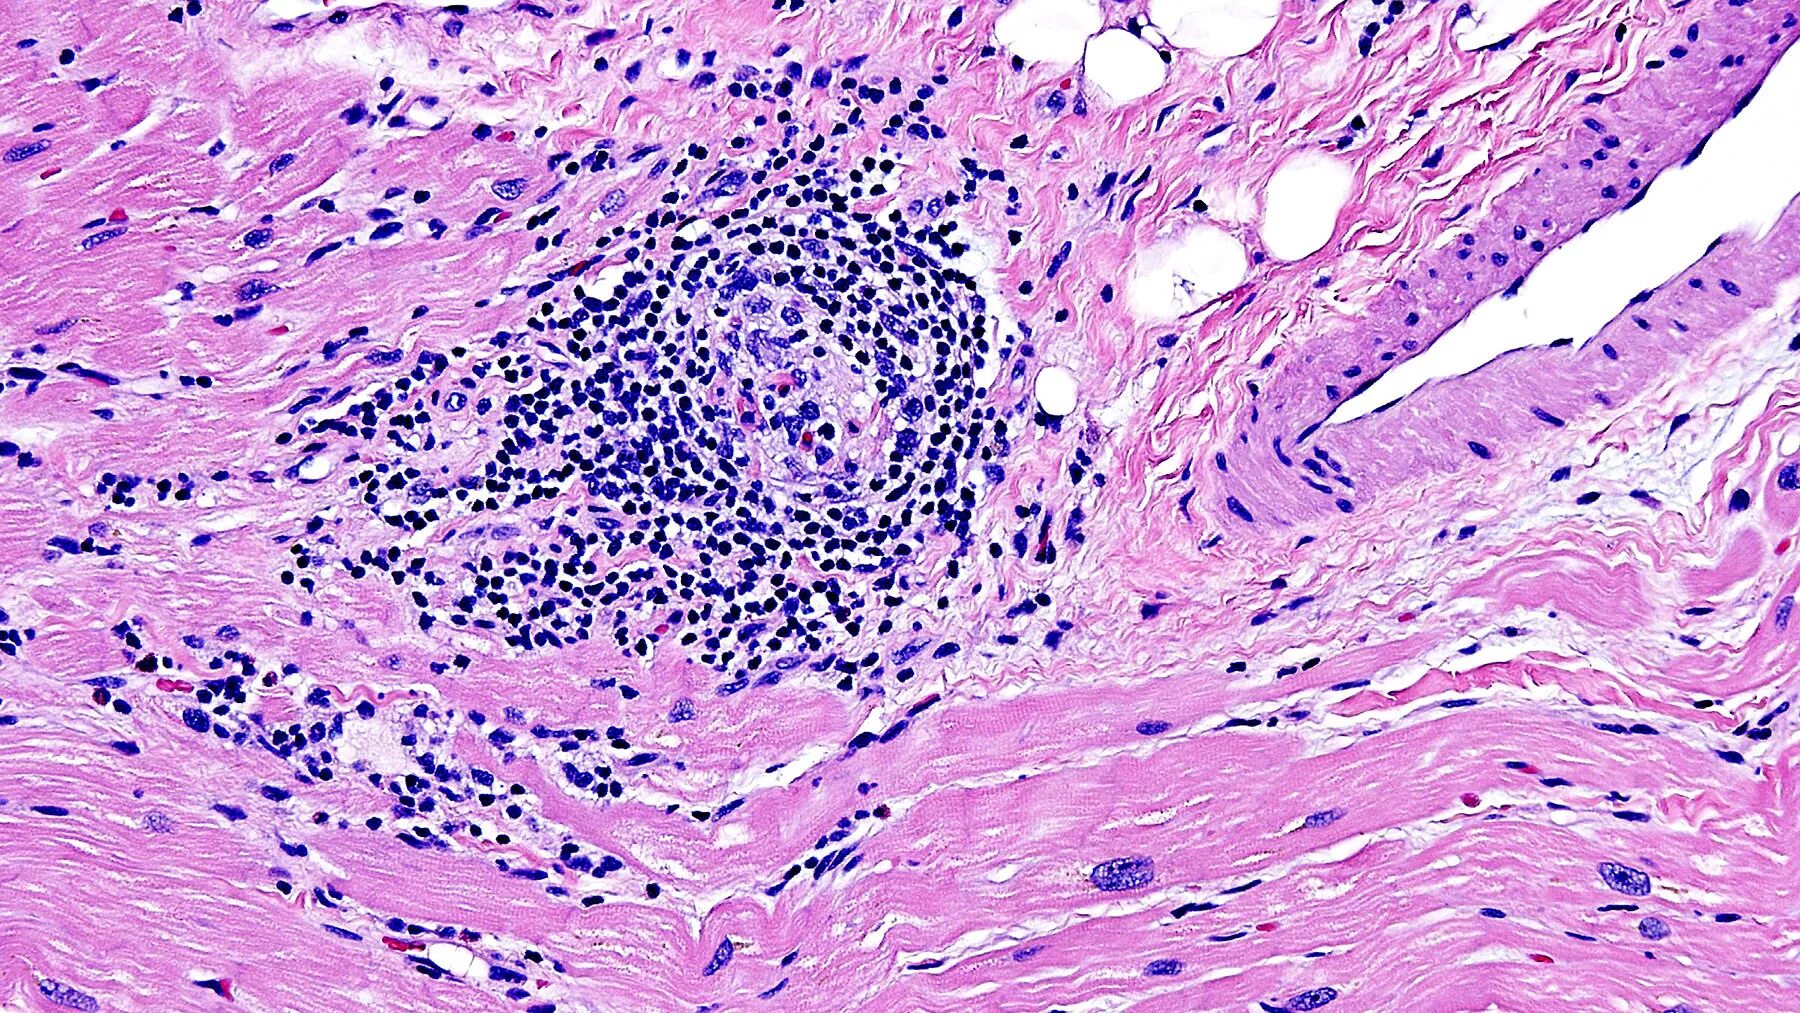

Инфильтрация в гистологии